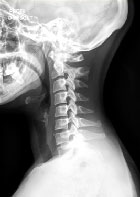

Un diagnostic souvent évoqué mais rarement retrouvé

Diagnostic et analyse des réponses

Nous avons reçu 193 réponses. Les diagnostics de « côtes cervicales ou apophysomégalie de C7 » ou « syndrome de la traversée » ont été proposés 130 fois. On peut noter cette anomalie sur le cliché de face.

D’autres anomalies sont visibles et ont été relevées...